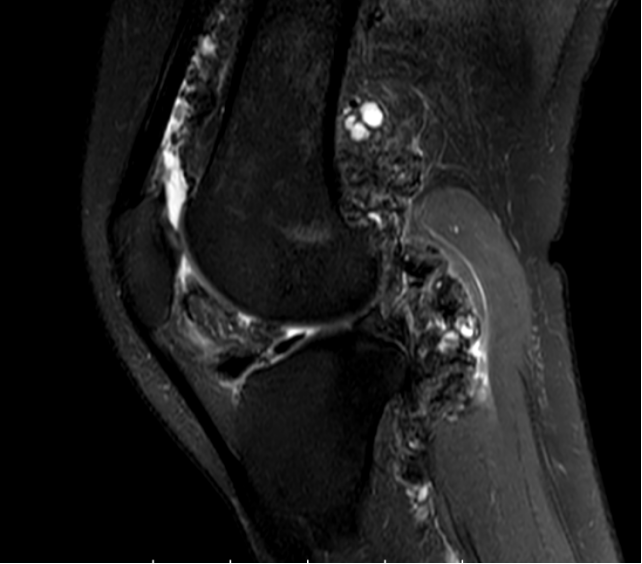

膝盖痛不一定是关节炎 有1症状恐是腱鞘巨细胞瘤 滑膜炎 Tgct 膝关节 大纪元